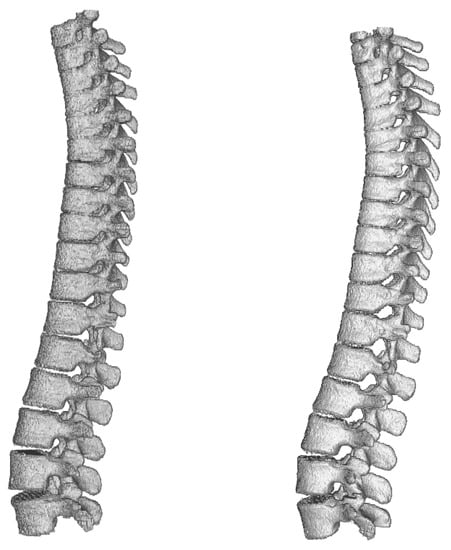

Dense-U-Net network has achieved the highest results in all metrics except for average Hausdorff distance. Reason for this is that the model does not perform well on borders of the image. In the dataset there were labelled only thoracic and lumbar vertebrae, but the CT scans contained also the first cervical vertebra and the network did include it in its segmentation results. You can see a part of the first cervical vertebra on top of the segmented spine in Figure 10.

Figure 10.

Comparison of ground truth model (left) and model segmented by Dense-U-Net network (right) after the fine-tuning phase of training. Notice difference on top of the figure—the first cervical vertebra and abnormal vertebrae adhesions that exist also in the original ground truth mask.

After accuracy of Dense-U-Net was verified to outperform the other architectures in the benchmark phase, we trained the network in the fine-tuning phase to achieve the best results possible, now using 99 epochs with weights initialized using pre-trained model. 3-folds cross-validation was used for evaluation. Results of the Dense-U-Net network in fine-tuning phase is depicted in Table 7. The visualisation of fine-tuned Dense-U-Net network result can be seen in Figure 10. Please notice that the abnormal vertebrae adhesions exist also in ground truth masks on the model in Figure 10 and therefore it is not a failure of the segmentation algorithm.